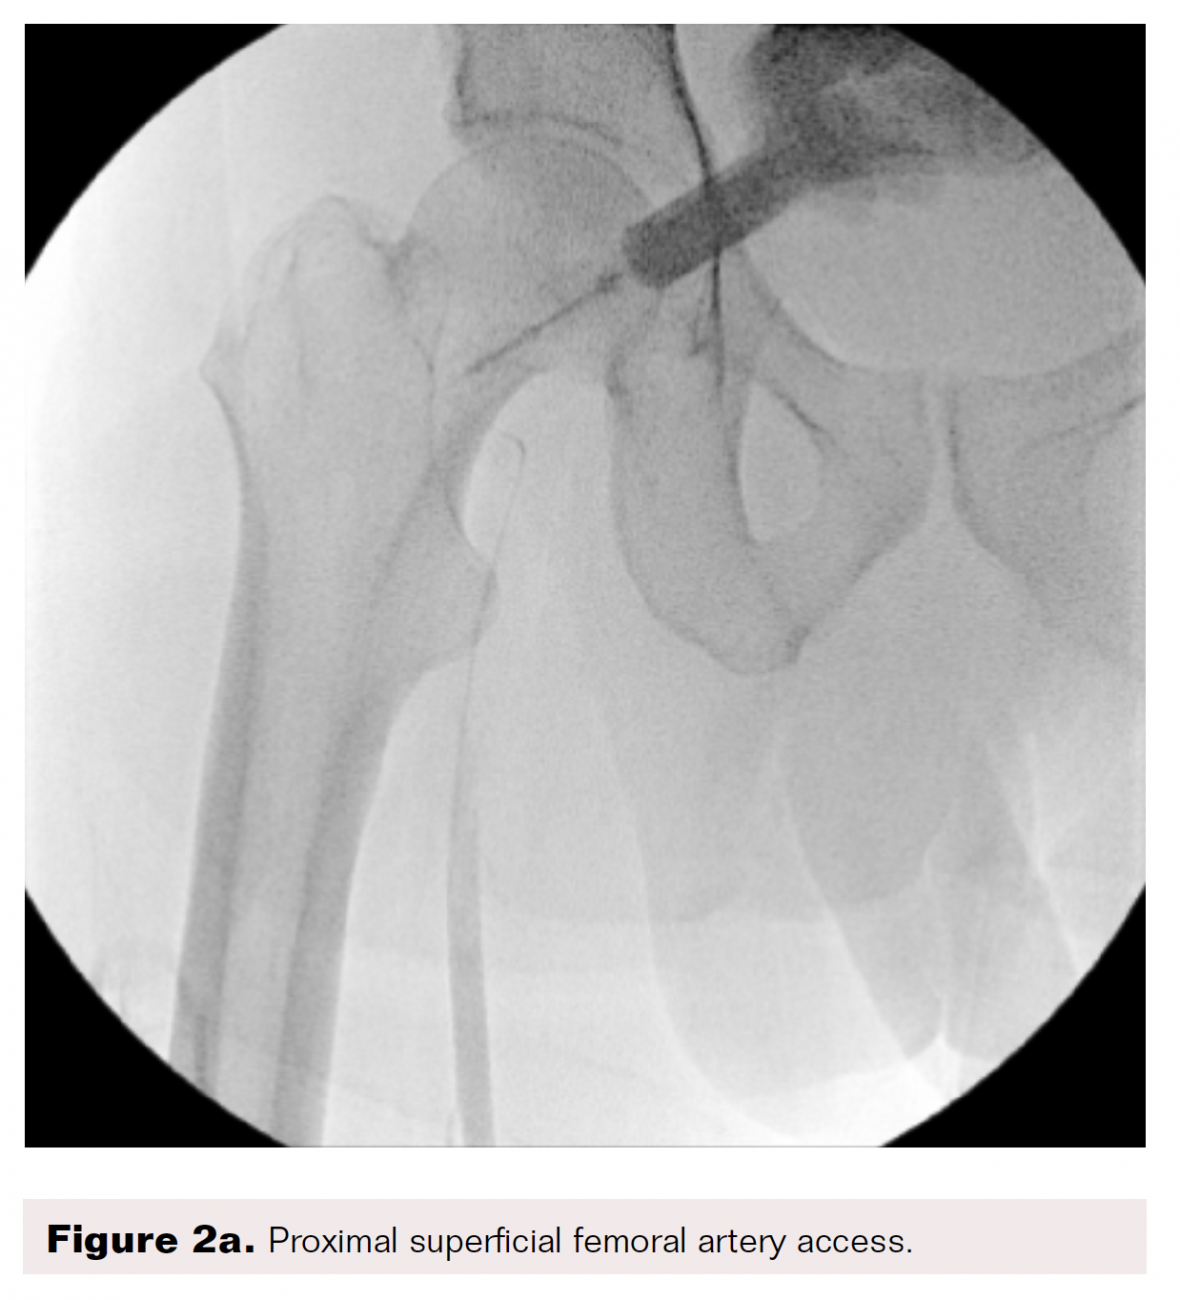

From www.hmpgloballearningnetwork.com

Pedal Revascularization Vascular Disease Management Pedal Disease Definition whenever severe pain occurs at the beginning of balloon inflation, especially at very low pressure (less than four. peripheral vascular disease (pvd) includes peripheral arterial disease (pad) and venous disease. Pad is a chronic progressive. peripheral artery disease (pad) is a common condition in which narrowed arteries reduce blood flow to the arms or. atherosclerotic lower. Pedal Disease Definition.